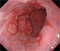

2026年1月24日開催の第19回研究会でご提示した検討症例です。 (画像をクリックすると拡大します)

2025年7月19日開催の第18回研究会でご提示した検討症例です。 (画像をクリックすると拡大します)

2025年1月11日開催の第17回研究会でご提示した検討症例です。 (画像をクリックすると拡大します)

2024年6月29日開催の第16回研究会でご提示した検討症例です。 (画像をクリックすると拡大します)

2024年1月6日開催の第15回研究会でご提示した検討症例です。 (画像をクリックすると拡大します)

2023年7月1日開催の第14回研究会でご提示した検討症例です。 (画像をクリックすると拡大します)

2023年1月21日開催の第13回研究会でご提示した検討症例です。 (画像をクリックすると拡大します)

2022年7月2日開催の第12回研究会でご提示した検討症例です。 (画像をクリックすると拡大します)

2022年1月22日開催の第11回研究会でご提示した検討症例です。 (画像をクリックすると拡大します)

2021年6月26日開催の第10回研究会でご提示した検討症例です。 (画像をクリックすると拡大します)

2021年1月23日開催の第9回研究会でご提示した検討症例です。 (画像をクリックすると拡大します)

2020年1月25日開催の第8回研究会でご提示した検討症例です。 (画像をクリックすると拡大します)

2019年1月12日開催の第6回研究会でご提示した検討症例です。 (画像をクリックすると拡大します)

2018年6月30日開催の第5回研究会でご提示した検討症例です。 (画像をクリックすると拡大します)

2017年7月15日開催の第3回研究会でご提示した検討症例です。 (画像をクリックすると拡大します)

2017年1月7日開催の第2回研究会でご提示した検討症例です。 (画像をクリックすると拡大します)

2016年6月4日開催の第1回研究会でご提示した検討症例です。 (画像をクリックすると拡大します)